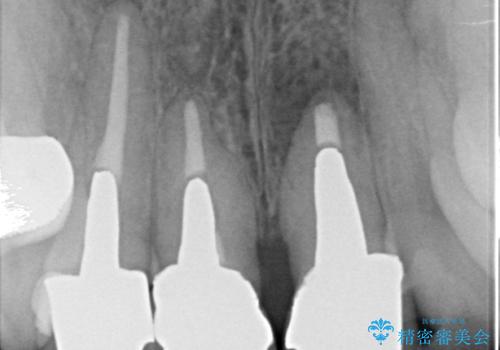

- 前歯の長さが違うのが気になるといらっしゃった方の症例です。

根尖病変を認めたため再根管治療を行った後、オールセラミッククラウン(スペシャル)にて補綴を行いました。